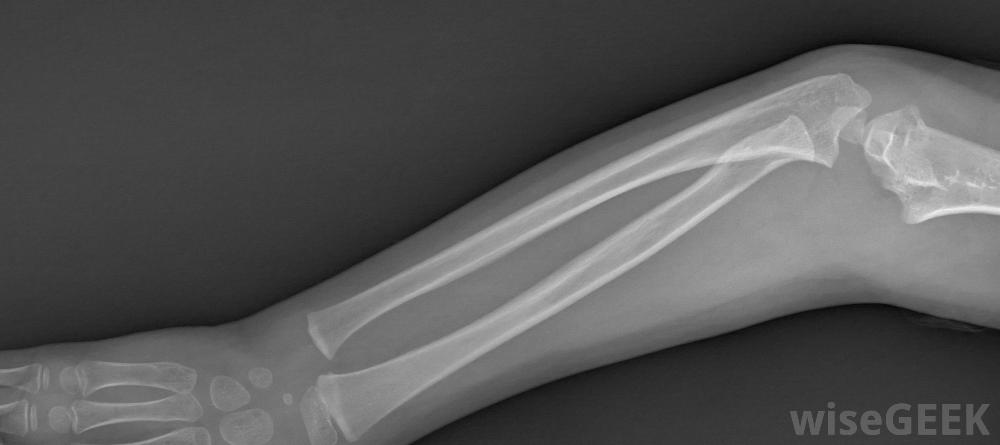

為了選擇最好的前臂夾板,你需要評估它能起到什么作用。手腕和前臂的許多損傷都涉及骨折或肌腱拉傷,但并非全部都有。有時損傷不是那么嚴重,或者是由于慢性問題,如腕管綜合征。如果你需要前臂夾板,然而,你幾乎總是需要某種保護和穩定的東西。糖鉗夾板在前臂骨折中很常見對于需要保護手臂不受電擊的損傷,最好的前臂夾板可能是充氣的。空氣墊通常會將夾板塑造成四肢的輪廓。它還對前臂施加均勻的壓力,保持血液循環,另一個優點是前臂空氣夾板通常是透明的,這意味著在接受x光檢查時可以不使用。但是,它可能會被鋒利的物體彈出,而且空氣夾板并不總能提供最好的通風前臂夾板通常是透明的,所以在拍x光片的時候就可以不用了。像腕管綜合癥或者網球肘這樣的病癥可以用空氣夾板來治療,但也有專門的支架,可用于這些情況下,將允許一些活動,同時保持一些穩定性和保護在肘部也受累的情況下,通常會使用長臂夾板來固定前臂和肘部。如果手指也需要穩定,則會使用專門的前臂夾板。這些夾板有固定手指的附件網球肘患者可能會從氣夾板中獲益。如果手臂骨折,你可能會得到掌側夾板或糖鉗夾板。夾板通常非常堅硬,由鋁、塑料或玻璃纖維制成,并有一個堅硬的金屬片來穩定。這些類型的夾板通常從手掌開始,沿著前臂向上,在到達肘部之前停止網球中使用的一些重復動作會給運動員帶來很大的壓力;前臂肌腱。這種特殊類型的夾板有許多變化。需要考慮的重要因素是易于拆卸和通風。一些前臂夾板完全包裹在手臂上,而其他人則暴露在開闊的地方,用門閂或Velcro?將堅硬的部件固定在適當的位置。Velcro?會更好地呼吸,但門閂可能會提供額外的保護層。如果您需要便宜或簡單的東西,并且只有一點點手腕或前臂受傷,使用帶Velcro?尼龍搭扣的簡單掌側夾板可能會起作用在前臂上纏上厚厚的布條繃帶也能提供輕微的穩定效果,而且通常更便宜,但是它不能呼吸。當你受傷時最好去看醫生,以確認損傷的程度,并確保你的前臂夾板適合你的情況肌腱拉傷的患者可以使用前臂夾板。